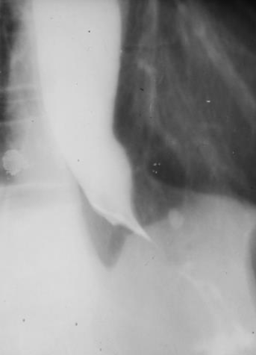

Diverticul Zenker